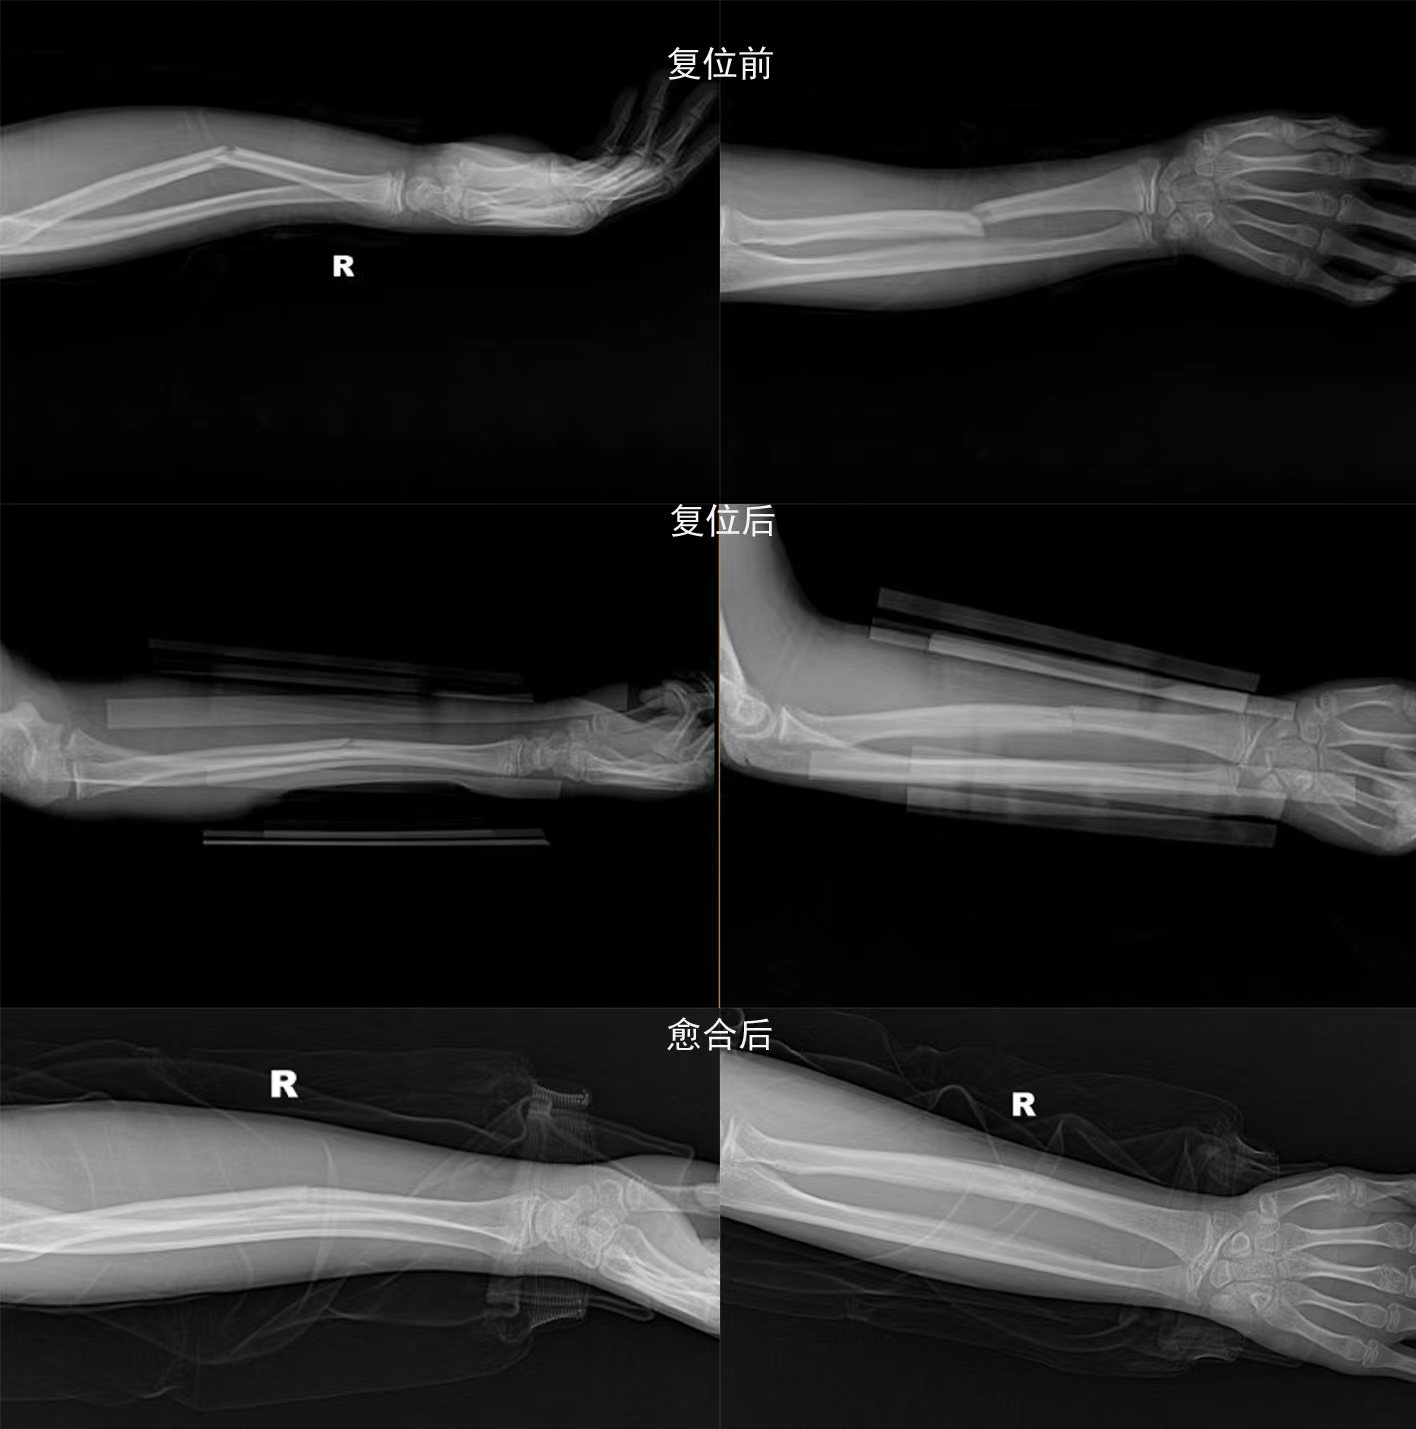

梁氏正骨-梁光兴正骨案例

梁氏正骨-杨乐正骨案例